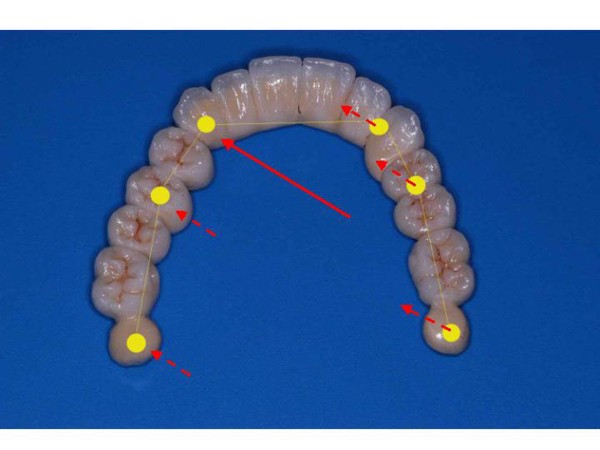

ABSTRACT La literatura oclusal se ha encargado de describir distintas funciones de la misma a través de los tiempos. El presente caso se realiza en forma de sobredentadura (over denture) debido a que la carencia de reborde óseo en el sector anterior verificado tanto clínicamente como mediante telerradiografía , impedía llevar a cabo una prótesis fija , por lo que se optó por un sistema de pilares ceramizados y paralelizados mediante el sistema SIRIUS, sobre seis implantes, y la conexión a una estructura de metal cerámica FIJA AMOVIBLE, mediante coronas telescópicas galvanizadas, otorgando al sistema la rehabilitación mediante una PIA(Prótesis Implanto Asistida con reposición ósea y gingival mediante porcelana rosa.) MATERIAL Y MÉTODOS: IMPLANTES:KLOCKNER SK-T.T.S. MONTAJE Y REGISTROS: ARCO FACIAL ESTÁTICO Y ARTICULADOR PRIMARIA: Abuttmets Ceramizados (I.P.S. D.SIGN IVOCLAR) SECUNDARIA: Cofias Galvanoformadas (AURO GALVAN CROWN WIELAND) TERCIARIA: Férula de Porcelana sobre Metal (I.P.S. D. SIGN IVOCLAR) CEMENTADO INTERFASE: NIMETIC CEM-ESPE DESARROLLO Se presenta el paciente a la consulta requiriendo la resolución de su maxilar inferior, el que se restaura mediante una férula de metal porcelana , en la que se preparan los lineamientos oclusales ideales (Spee-Wilson-Cuatro Niveles-etc) a fin de tener un sustrato de trabajo correcto, para la confección del maxilar superior, que porta una Prótesis Total convencional. Se estudia mediante Panorámica, Dentascan y Montaje en articulador semi ajustable. Se instalan seis implantes Klockner con Técnica Semisumergida pensados para una Carga diferida a tres meses después de la implantación Se realiza el arrastre de los Transfer mediante cubeta individualizada y fenestrada. Se confeccionan los abuttmentes correspondientes y se llevan a boca mediante una férula de posicionamiento realizada en Acrílico Duralay, el que por sus condiciones de carencia de cambios volumétricos verifican el correcto ajuste de los mismos Se ceramizan los abuttments y se paralelizan mediante el sistema SIRIUS, llevándolos a boca y chequeando su instalación Se confecciona una Prótesis Total Provisional que llevará el paciente durante el período de Osteointegración Se procede a la confección en laboratorio de las cofias galvánicas Sobre un nuevo modelo mayor se confecciona la férula de metal que uniremos en boca a las cofias galvanizadas mediante un cemento especial, una vez confeccionada la porcelana. Se prueba en boca la férula metálica, verificando su holgura que será ocupada por el cemento antedicho, y se comienza con el montaje de la cerámica y la verificación de los patrones oclusales de la misma. Se instala el todo haciendo morder al paciente con el medio cementante instalado. FIGURA 40 FIGURA 41 FIGURA 42 CONCLUSIONES La función de «GUIA CANINA», como esquema mas propicio para cumplir con los deseos de «autoprotección » de un SEG, rehabilitado o no, no se cumple al 100 % en casos como el presentado. La razones por las cuales el uso de la misma en lo que se da en denominar OCLUSIÓN MUTUAMENTE PROTEGIDA consiste en tres factores que detallo a continuación: A. En una función desoclusiva realizada por las piezas anteriores, como por ejemplo el canino, el BRAZO DE RESISTENCIA generado en la palanca desoclusiva, es por lo menos igual al brazo de potencia desarrollado, argumento de gran peso para hablar de la Desoclusión Canina como esquema de elección- B. La inclinación de los rebordes marginales del canino superior, esta dentro de los 70º, a diferencia de la tabla oclusal posterior que puede variar entre los 20 y 40 º. C. El estimulo que generan los dientes anteriores se dirige por via aferente al SNC, exitando por vía eferente, fundamentalmente al músculo temporal en sus fibras anteriores o VERTICALES…fibras de mucha menos capacidad de fuerza, que si la acción la ejercieran las fibras de la cincha PTERIGO MASETERINA, que serían exitadas en el caso de una Función de Grupo. EN EL CASO PRESENTADO LAS DOS PRIMERAS RAZONES TIENEN VIGENCIA. Sin embargo la última de ellas , al no tener los Implantes terminaciones nerviosas como las que posee el periodonto , los estímulos que llegan al SNC no se cumplen, y por lo tanto no existe la respuesta que por conducción eferente estimularía al músculo temporal a su acción. De la misma manera, el hecho que estos Implantes estén ferulizados , trasmite fuerzas laterales también a los posteriores, y no solo a los que actúan como caninos. El beneficio de las dos primeras razones de uso de una Función Canina en un caso como este, obedece a que de por si las mismas minimizan la acción direccional de las fuerzas, las que sin embargo son compartidas por las piezas posteriores tanto del LT como del LnT. En este compartir de la función, me resulta conveniente denominar a este esquema: FUNCIÓN DE GRUPO POSTERIOR DE ACCIÓN CANINA. ———————————————————————————————————- PIE DE FOTOS: 37: CASO TERMINADO

38: OCLUSIÓN EN RELACIÓN CÉNTRICA

39: LATEROTRUSIÓN IZQ.

40:LADO NO TRABAJO

41:LATEROTRUSIÓN DER.

42:LADO NO TRABAJO